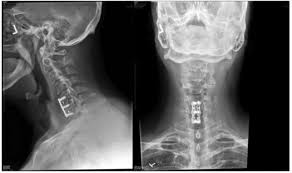

In spite of making rapid strides in healthcare in the last few decades, tuberculosis is still a very common problem in India, Bangladesh, Afghanistan, Pakistan as well as Africa. A bug called Mycobacterium tuberculosis causes TB. Bone TB is the next most common site after lungs. Amongst bones, it is the spine (neck and back) that is the most common site of tuberculosis. Tuberculosis can strike anyone at any age and there may be no specific predisposing factor in most patients. Children and elderly; people with decreased immunity; family history or past history of tuberculosis and patients who have had contact with a known case of tuberculosis are some groups that are prone to developing tuberculosis. Tuberculosis can affect any part of the spine from the upper neck to the tailbone.

The good news is that most cases of spinal tuberculosis can be completely cured just with standard anti tuberculosis medicines. Once a diagnosis of spine tuberculosis is confirmed, your doctor will start you on anti TB treatment (ATT) for 9-12 months. This will typically comprise of 4 drugs – Isoniazid, Rifampicin, Pyrazinamide and Ethambutol. More than 90% patients improve on ATT but a few patients may need Spine Surgery in addition to ATT.